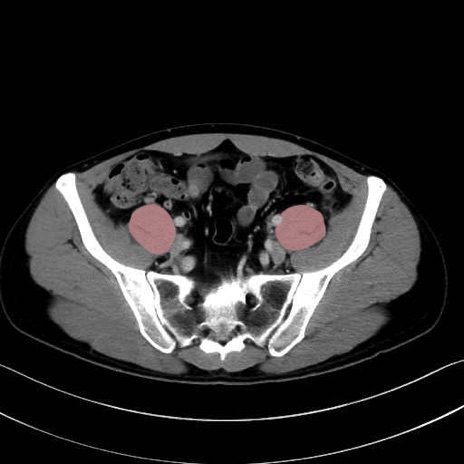

2. 腸腰筋群と骨盤底筋

大腰筋 (Psoas major)

腸骨筋 (Iliacus)